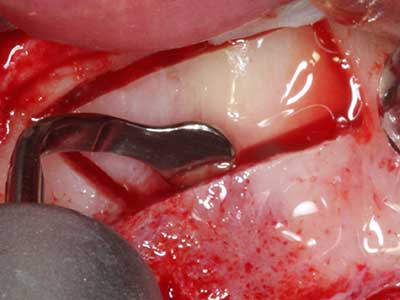

Sollen chirurgische Eingriffe mit unmittelbarer Knochenbeziehung an empfindlichen Strukturen wie Blutgefäßen oder Nerven erfolgen, so bergen rotierende Instrumente ein erhebliches Potential an iatrogener Schädigung. Gerade bei Nervdarstellungen nach iatrogener Schädigung, oder aber im Zuge einer Nervlateralisation für resektive und rekonstruktive Eingriffe oder Implantatinsertionen können piezoelektronische Geräte hilfreich sein Knochendeckel zu präparieren und nervnahe Hartgewebsanteile zu entfernen (Abb. 17-20). Ein leichter Kontakt des Nervstrangs zur Piezospitze bleibt dabei in der Regel folgenlos – allerdings kann eine unvorsichtige Vorgehensweise mit sägeartigen Bewegungen bzw. Ansätzen bei noch vorhandener knöcherner Unterlage durchaus temporäre oder aber auch permanente Nervschädigungen verursachen. Das Risiko einer solchen Schädigung wird jedoch als wesentliche geringer eingeschätzt als unter Anwendung von Säge- oder Fräsinstrumenten (Pereira, Gealh et al. 2014).

Indikation: Parodontaltherapie